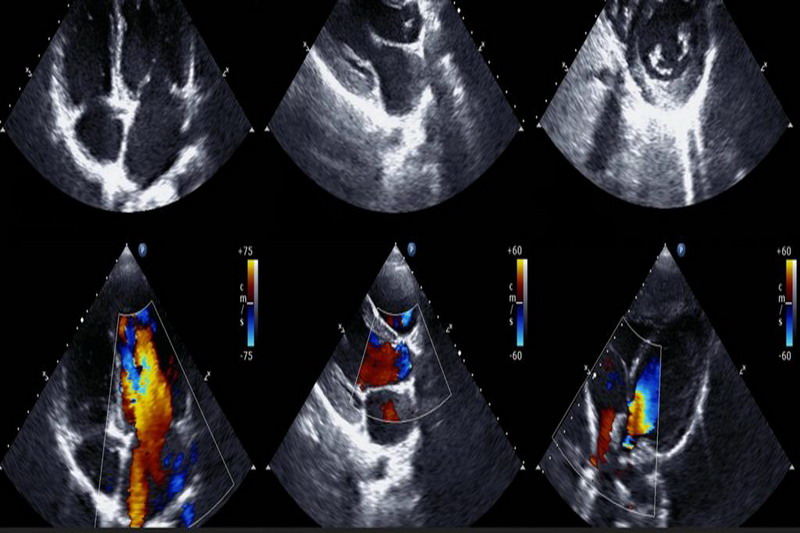

ECOGRAFIA CARDIACA TRANSTORACICA

Este o investigatie medicala nedureroasa, non-invaziva care furnizeaza date despre dimensiunile si functia inimii, valvelor cardiace.